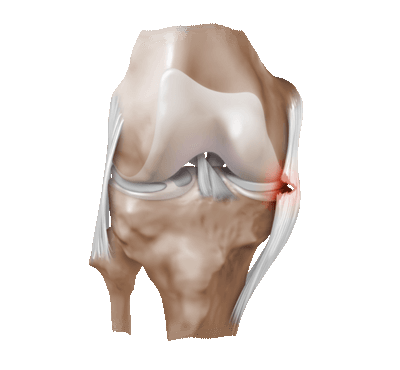

1. Целостность мениска и состояние его периферической зоны (рис. 1 и 2):

• Остатки нативного мениска можно использовать в качестве шаблона для определения размеров необходимого трансплантата мениска